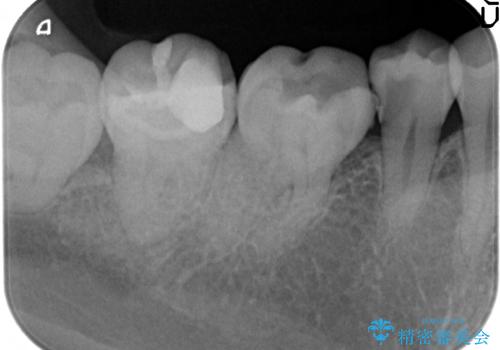

- 右下の奥歯がズキズキ痛むので診て欲しいといらっしゃった方の症例です。

右下5は虫歯が大きく神経は保存不可能だったため、根管治療を行った後、オールセラミッククラウンによる補綴を行いました。

虫歯治療は虫歯の進行度によって処置が変わってきます。

虫歯が小さければ、インレー・クラウン等による修復・補綴処置を行うだけで済みます。

しかし虫歯が大きくなると神経処置や抜歯等をしなければならない場合もあります。